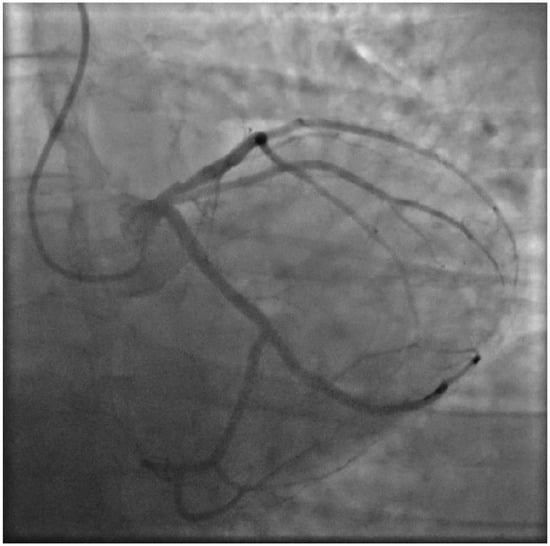

2. Case Presentation